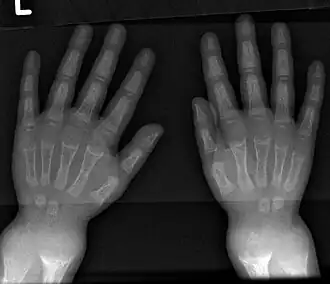

An X-ray or radiograph of an advanced patient with rickets tends to present in a classic way: the bowed legs (outward curve of long bones of the legs) and a deformed chest. Changes in the skull also occur, causing a distinctive "square-headed" appearance known as "caput quadratum".[20] These deformities persist into adult life if not treated. Long-term consequences include permanent curvatures or disfiguration of the long bones, and a curved back.[21]

- Radiography typically shows widening of the zones of provisional calcification of the metaphyses secondary to unmineralized osteoid. Cupping, fraying, and splaying of metaphyses typically appear with growth and continued weight bearing.[50] These changes are seen predominantly at sites of rapid growth, including the proximal humerus, distal radius, distal femur, and both the proximal and the distal tibia. Therefore, a skeletal survey for rickets can be accomplished with anteroposterior radiographs of the knees, wrists, and ankles.[50]